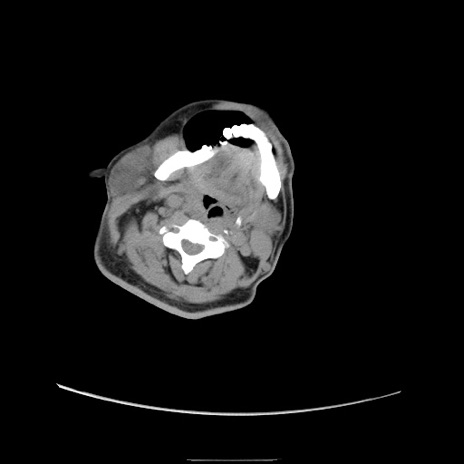

冠状断像

【症例】50歳代男性

【主訴】腹痛

【現病歴】AVMからの被殻出血のため回復期リハ病棟入院中。 本日午後3時頃急に下腹部痛が出現した。

【既往歴】AVM、被殻出血、虫垂炎、高血圧

【身体所見】意識晴明、左半身不全麻痺、会話の理解は良好、36.5°C、腹部:膨隆、全体に板状硬、下腹部正中に圧痛点あり、反跳痛-、筋性防御不明、右下腹部にope scar

【データ】WBC 9400、CRP 0.06